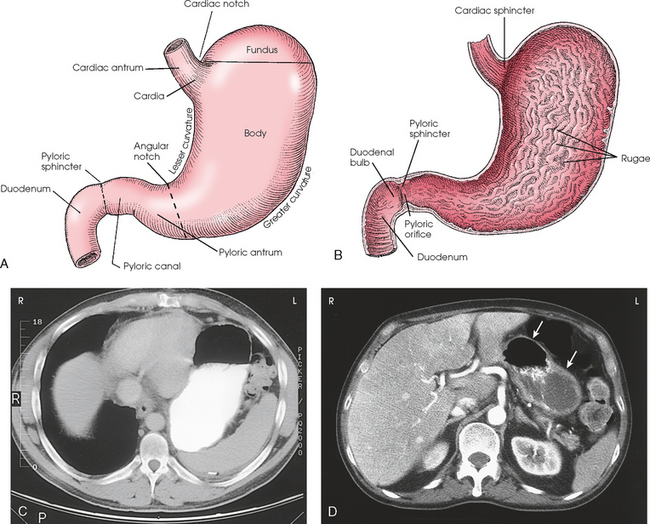

Gastric cardia radiology. Diagnostic centers of america dca is a leading diagnostic imaging facility offering a full array of imaging services in palm beach county florida. We have five state of the art radiology imaging centers in boca raton boynton beach delray beach and wellington florida. The gastric cardia is characterized on barium stud ies by three or four stellate folds that radiate to a central point at the gastro esophageal junction also known as the cardiac rosette fig 2 12. Variations and benign influences may closely resemble the more dangerous lesion.

Cain jc jordan gl jr comfort mw gray hk. J am med assoc. The gas tric fundus is dened as the portion of the stomach craniad to the gastric car dia. Commonly accompanying this are abnormally dilated short gastric veins which pass from the splenic vein to encircle the gastric fundus and form gastric fundal varices.